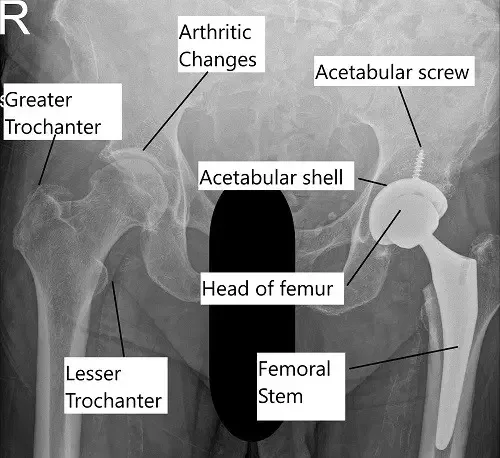

X-ray showing a total hip replacement surgery.